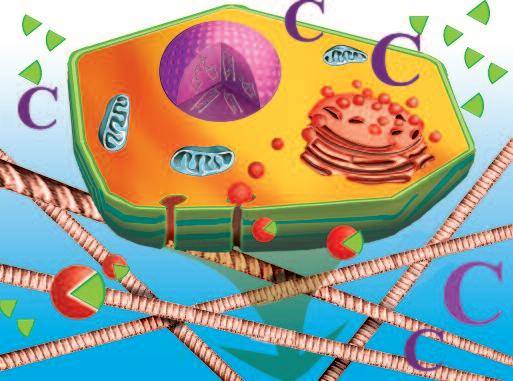

Normalmente, le cellule del nostro corpo sono inserite in una rete di collagene e di altre molecole del tessuto connettivo che le mantengono al loro posto. Affinché le cellule tumorali possano crescere, divenendo un tumore, e possano diffondersi in tutto il corpo, è necessario fendere questo isolamento del tessuto connettivo. A questo fine, ogni cellula del cancro produce ‘forbici biologiche’, ovvero degli enzimi proteolitici in grado di digerire il tessuto connettivo che circonda le cellule tumorali.

Una delle più importanti molecole secrete dalle cellule tumorali in grandi quantità sono gli enzimi a ‘forbice’ che digeriscono il collagene. Sono aggiunti graficamente a questa immagine, sotto forma di strutture simili ad un ‘pacman’ rosso.

“Forbici biologiche” – Enzimi

Sostanze

da tutte le cellule tumorali

At tivatore plasminogen o (Urochin asi)

Compito di questa serie di reazioni in cascata è la digestione del tessuto connettivo Reazi oni in cascata per la digesti one

Naturalmente questi sfere, nella vita reale, sono molecole biologiche, proteine, che hanno la capacità di tagliare le fibre di collagene e di altre molecole del tessuto connettivo. L‘immagine sopra mostra che non c’è un solo tipo di 'pacman' ovvero di queste molecole, ma

Plasmin ogeni

Metal loproteinasi (MMP)

Digestione del tessut o connet tivo del tessuto connetti vo diversi tipi, quali il plasminogeno/plasmina e le metalloproteasi (strutture colorate tridimensionali). Queste molecole migliorano il loro effetto distruttivo attivandosi reciprocamente in forma di reazione a catena in cascata.

Le collagenasi, gli enzimi che digeriscono il collagene, sono prodotte da tutte le forme di cancro, indipendentemente dalla loro origine. L’illustrazione delle pagine a fianco mostra un esempio di questo processo: lo sviluppo del cancro al fegato.

Il fegato è l’organo centrale del metabolismo del corpo e, tra gli altri, è responsabile della neutralizzazione e della eliminazione delle tossine dal corpo. Tossine quali pesticidi, conservanti e molte droghe sintetiche farmaceutiche, sono le cause più comuni del cancro al fegato. Le cellule del fegato esposte a queste sostanze tossiche possono essere danneggiate o distrutte in modo permanente. La forma più frequente di danni porta ad una falsa ‘programmazione’ del materiale genetico della cellula (DNA).

Tale alterazione maligna del software della cellula segna l’inizio del processo tumorale attivando una serie di azioni biologiche che alla fine porta al cancro vero e proprio. Alcune di queste azioni sono essenziali per la crescita e la diffusione del cancro:

1. Moltiplicazione incontrollata delle cellule. Il software di una cellula tumorale è alterato in modo tale da rendere ‘immortale’ questa cella e farla moltiplicare all’infinito.

2 La produzione di massa di enzimi che dissolvono il collagene Il secondo presupposto del cancro è la produzione di enzimi che distruggono il tessuto connettivo circostante che, altrimenti, manterrebbe il tumore confinato.

Più enzimi che digeri scon o col lagene p rodu ce una cellula tumoral e, più aggressivo è il cancro e più velocemen te si diffon de attraverso il corp o, e più breve di venta l'asp ettativa di vita del paziente, semp re se tale meccan ismo non viene arrestat o.

Tumore al fegato

Cellule epatiche:

• Cellule sane (marroni)

• Cellule tumorali (verdi)

Le cellule tumorali presentano il software del nucleo alterato, questa modifica non prevede l’apoptosi (la morte fisiologica della cellula in caso di malfunzionamento o invecchiamento)

Le cellule tumorali

• si moltiplicano e

• producono collagenasi. Entrambe le produzioni sono stimolate senza limiti

Il disegno mostra gli enzimi prodotti dalle cellule tumorali epatiche che si fanno strada per espandersi.

La produzione di enzimi che digeriscono il collagene è il denominatore comune di ogni specie di tumore per crescere ed espandersi – è indifferente in quale organo la malattia compare.